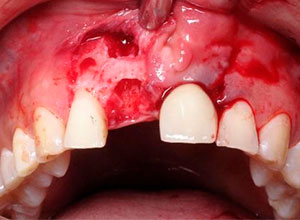

Paciente femenino a la cual le colocaron implante alto verticalmente, presentando a la vista una corona con un excedente de aproximadamente 5 milímetros, de porcelana rosa.

La paciente inconforme con los resultados nos visita, realizamos estudios radiográficos y tomográficos, encontrando que se perdió hueso verticalmente en el implante.

Decidimos hacer una corticotomia alveolar, dejando tejidos blandos en su lugar y cambiar la corona de cerámica por una corona de acrílico para cementar bien los brackets y poder empezar con la distracción.